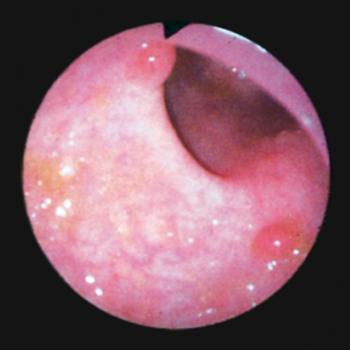

This article will review the current practice of hepatic resection for colorectal liver metastases, including the possibility of combined resection of hepatic metastases at the time of resection of the primary cancer.